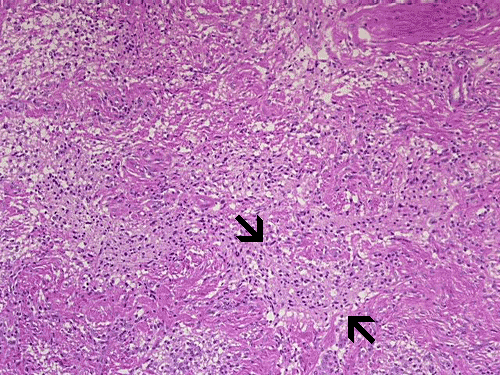

On low-magnification, cross section of the optic nerve gives a "double barrel" structure. The general outline of an optic nerve can still be appreciated (delimted by Þ in Panel A). There is a moderately cellular population of cells in between the dural sheath ( in Panel A) and the optic nerve. On medium-magnification, the vascular septa of the optic nerve is preserved (Panel B). On high-magnification, the optic nerve contains a mixture of cells with enlarged, mildly pleomorphic nuclei that are neoplastic astrocytes. Some cells with small nuclei are present and probably represent residual and reactive non-neoplastic astrocytes (Panel C and D). Cytoplasmic processes of some of tumor cells appear finely fibrillary (Panel C) while others are corase (Panel D). The cells in between the optic nerve and the dura is a mixture of irregular, hypercellular islands of neoplastic glial cells (delimted by Þ in Panel E) and hypocellular islands of slightly eosinophic, spindle cells. The later population represents reactive proliferation of meningothelial cells. The cytologic features are better appreciated in high-magnification (Panel F).

Microscopically, ONG in children are almost all pilocytic astrocytomas. The optic nerve is expanded. The fibrovascular septa within the optic nerve are separated by the tumor cells but the structure can still be well recognized as an optic nerve on cross section. Three major patterns are recognized 1. In the first pattern, the tumor is finely reticulated. In the second pattern, the tumor has microscysts and is coarsely reticulated. In the third pattern, the tumor cells are coarsely fibrillated, spindle shaped, and form bundles. There is minimal pleomorphism in the nuclei and it is not always easy to separate the neoplastic cells from adjacent reactive gliosis. There is a usually lack in mitotic activity, endothelial proliferation, and necrosis. Immunohistochemistry, the tumor cells are strongly reactive for glial fibrillary acidic protein (GFAP).

ONGs often extend into the subarachnoid space and inflict a prominent proliferation and thickening of perioptic meninges. This proliferation is composed of meningothelial cells, fibroblasts, and neoplastic astrocytes. Such changes are also known as arachnoidal hyperplasia or arachnoidal gliomatosis. The tumor tends to have coarsely fibrillated spindle cells may not be easily to be separated from the meningothelial cells and fibroblasts due to the intermingled architecture. Immunohistochemistry for GFAP is very helpful in separating the two components.